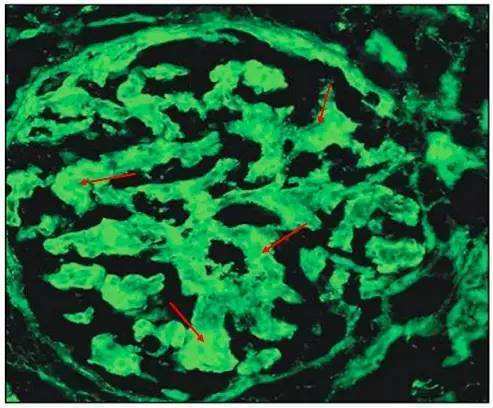

图 27 红色箭头:fibronectin 在肾小球系膜区呈条索状沉积